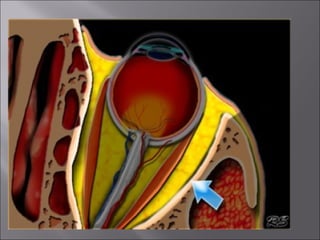

Ultrasound and CT scans provide anatomical images of the orbit, while color Doppler imaging provides visualizations of vascular structures and blood flow within lesions. These imaging techniques are used to evaluate a variety of orbital conditions involving blood vessels, infections, tumors, congenital issues, trauma, and more, and can help identify vascular disorders, thrombosis, treatment responses, and dynamic changes in benign tumors over time.